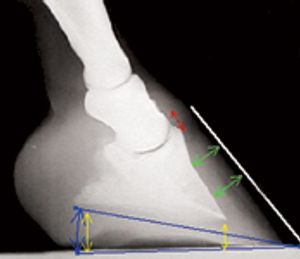

Solving the mathematical needs of a Grade IV laminitic foot.

How to meet the mathematical needs of the higher grades of laminitis.

The mathematical needs of lower grades of laminitis.